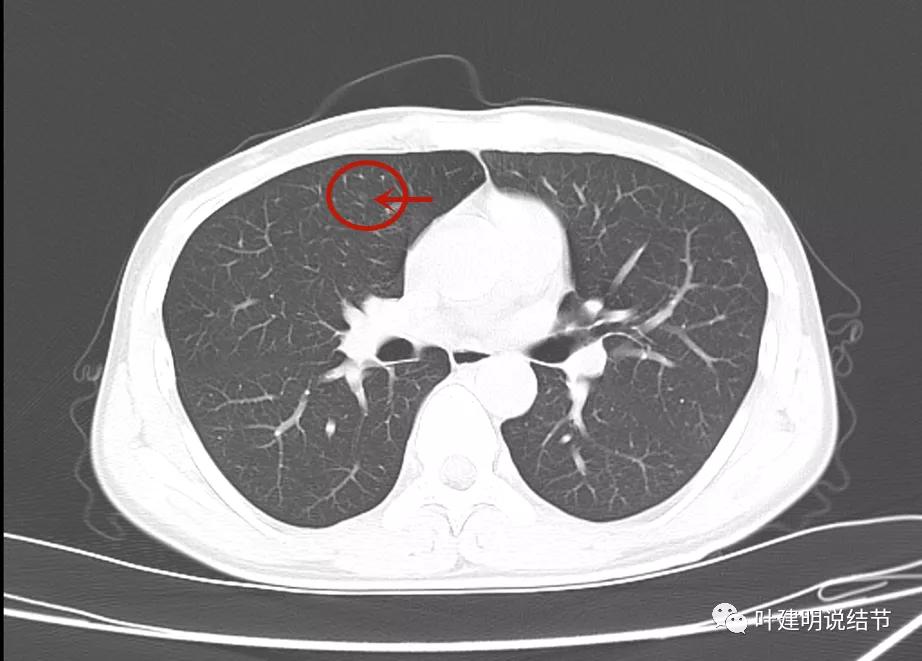

此后不知道为什么试验性抗结核治疗2个月,我感觉结核不太像吧?下面是2022年1月复查的:

病灶1没有明显变化

病灶2也仍在,微血管征仍较明显,病灶本身淡而小

病灶3未见明显显示。

但又有个缺陷,这次又不是薄层扫描。我们能认为病灶3吸收了吗?我觉得是不能够的,刚好没有扫到的可能性大。如果真的是结核,病灶3消失了,病灶1与病灶2也该有所吸收好转呀。所以基本不可能是结核药把病灶3吃好了。